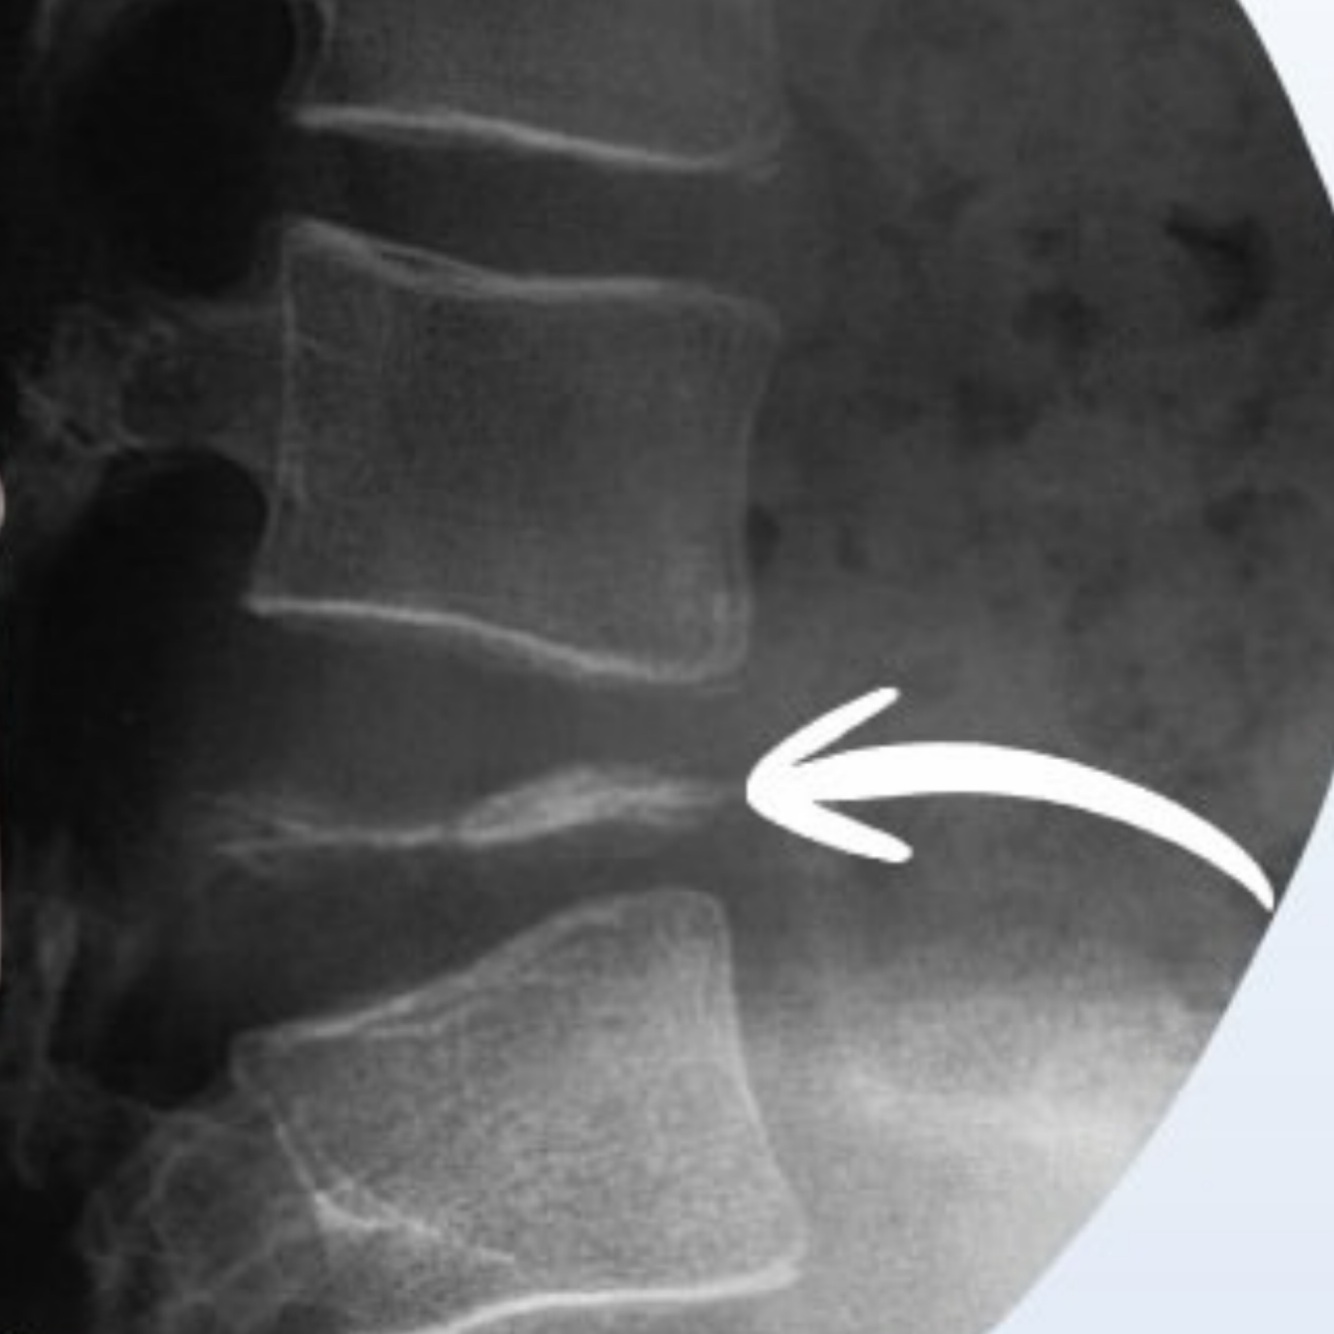

Qual alteração evidenciada?

A

Osteófito

-o osteófito tende a ser horizontal, numa tentativa de aumentar o platô vertebral

- há desidratação com redução do espaço discal e outras alterações degenerativas